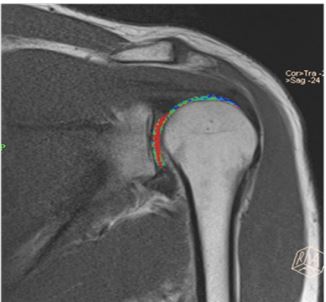

We obtained the higher T2 value in the post-processing image of T2 relaxometry sequence (Figure 2b) at the superior glenohumeral cartilage and were co-related with Figure 2. We used the rainbow scale (Figure 3a & b) in colour map post-processing techniques, where blue indicates higher T2 values and red indicates lower T2 values according to the references [2,3]. The standard T2 relaxometry value of the cartilage is 32.1-35 ms and that in mild and severe osteoarthritic changes of the cartilage is 34.4-41.0 ms and >45 ms, respectively. However, in this case, the T2 values were 45-60 ms (>45 ms) which correlates with the colour maps. Hence, there is an early degeneration of the cartilage (early osteoarthritis) which was difficult to discern in standard greyscale images

Figure 2A: : Color mapping (Glenohumeral cartilage -coronal plane).

Figure 3a: Color mapping of the glenohumeral cartilage.

Figure 3b: Colour scale [1]-Blue -higher T2 values (More relaxation time), Green to Orange -medium T2 values (Medium relaxation), Red -short T2 values (short relaxation times).